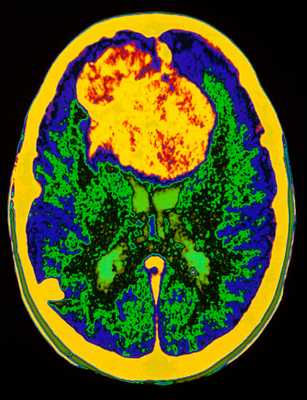

МРТ головного мозга. Аксиальная Т2-взвешенная МРТ. Цветовая обработка изображения. Опухоль мозга.